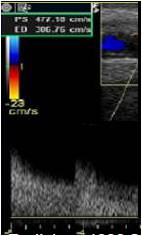

目前颈动脉狭窄非创伤影像检查工具主要有: ![]() 超声 超声颈动脉狭窄可以发现颈动脉狭窄患者的颈动脉有无回声、混杂回声和溃疡形成。 颈动脉狭窄超声表现